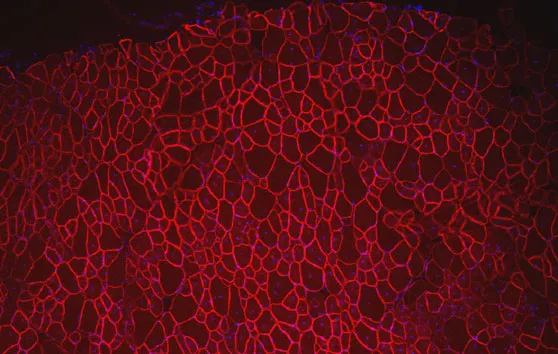

Interactome : un outil pour étudier les protéines des myopathies des ceintures

Généthon a étudié les interactions entre des protéines des myopathies des ceintures et d’autres protéines de l’organisme. Ces liens forment un réseau dense appelé Interactome.